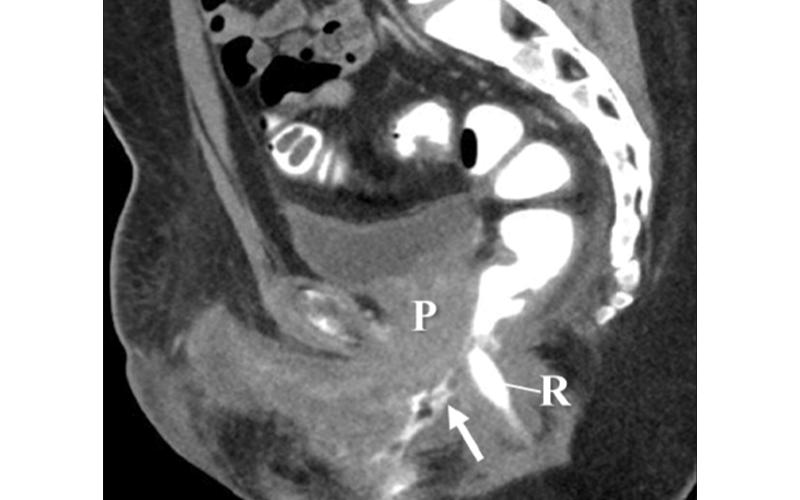

Therefore, changes after hysterectomy might be misinterpreted as the patient having a prostate if care is not taken during interpretation to assess the pertinent history. Conversely, the prostate is not removed during vaginoplasty in transfeminine patients, so a radiologist might misinterpret its presence as representing a mass.